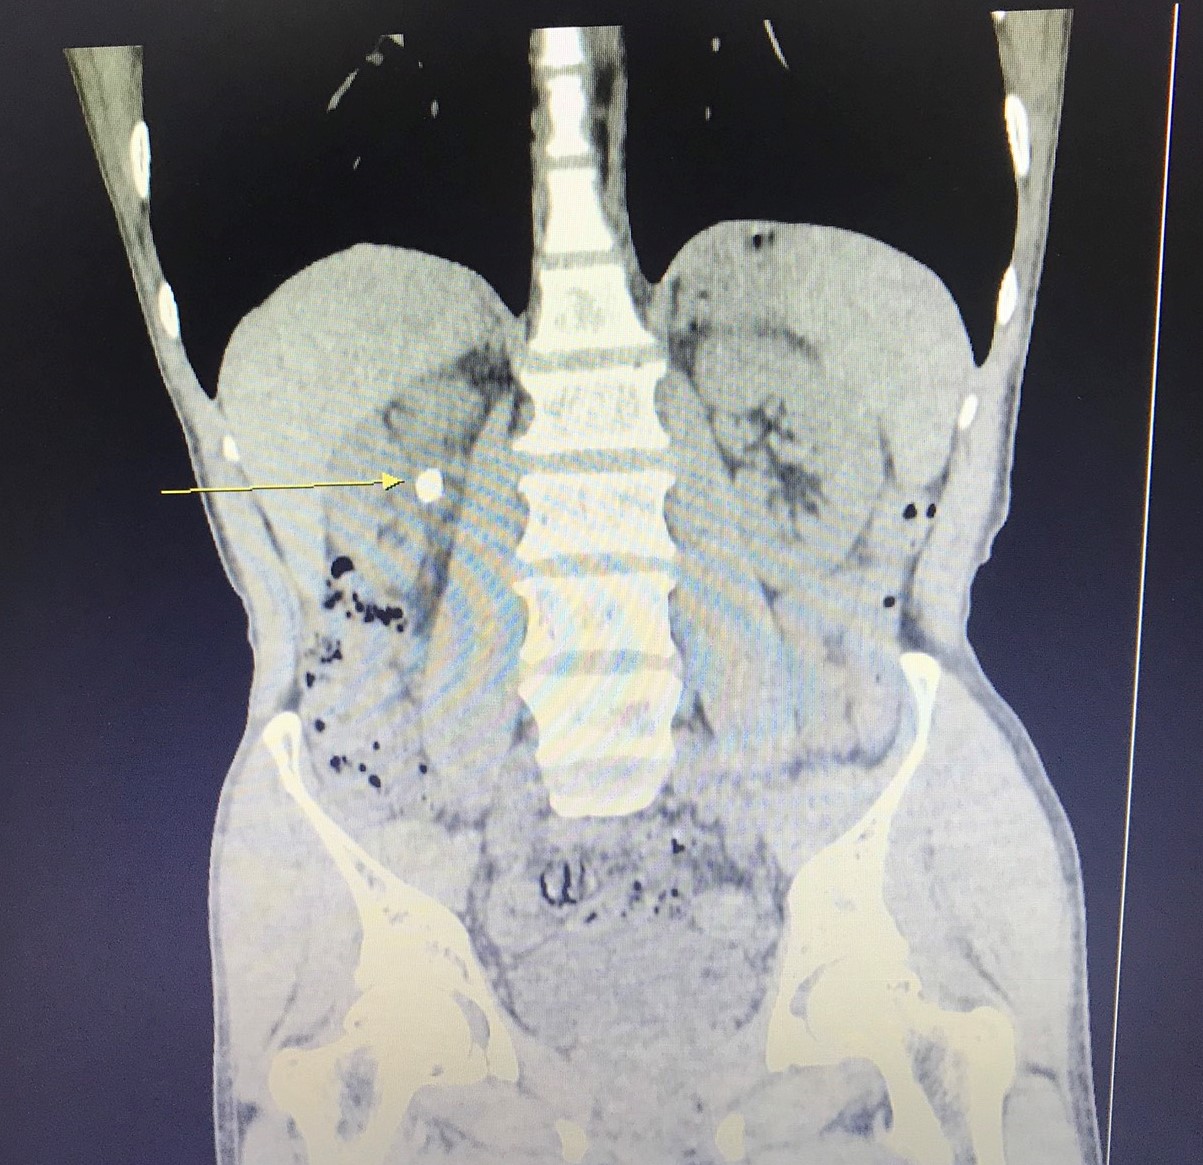

Bệnh nhân N.V.T, 58 tuổi, ở Cấp Tiến, Tiên Lãng, Hải Phòng có sỏi ở khúc nối bể thận – niệu quản phải kích thước 16x8mm gây ứ nước thận phải độ I, giãn đài bể thận phải, bệnh nhân có chỉ định tán sỏi ống mềm bằng laser. Ca phẫu thuật được TS.BSNT Phạm Việt Hà – Giám đốc chuyên môn, Trưởng Khoa Ngoại thận Tiết niệu – Nam học, Bệnh viện đa khoa Quốc tế Hải Phòng trực tiếp thực hiện. Chỉ trong vòng 30 phút, sỏi đã được tán vụn hoàn toàn và sau đó các mảnh sỏi được đưa ra ngoài qua đường bài xuất nước tiểu. Bệnh nhân gần như rất ít đau, có thể đi lại, tự chủ vệ sinh cá nhân ngay trong ngày đầu sau phẫu thuật.

Tán sỏi ống mềm là kỹ thuật được thực hiện bằng việc đưa ống soi mềm ngược dòng qua đường tiểu lên niệu quản – bể thận, vào các đài thận để tìm sỏi, tiếp cận trực tiếp viên sỏi và tán vụn sỏi bằng laser. Được đánh giá là kỹ thuật cao, chuyên sâu chỉ định cho bệnh lý sỏi thận, sỏi đường tiết niệu với kích cỡ sỏi nhỏ từ 10mm – 30mm ở các vị trí: sỏi 1/3 trên niệu quản, sỏi nhóm đài dưới song cổ đài phải rộng, sỏi nhóm đài trên, sỏi ở bể thận. Với kỹ thuật này, bác sĩ dùng ống mềm đi từ niệu đạo vào niệu quản và ngược dòng lên bể thận, góc quan sát rộng lên tới 360 độ kết hợp với năng lượng Laser mạnh nên gần như những sỏi với kích thước 10-30mm được phá hủy, tán vụn hoàn toàn.